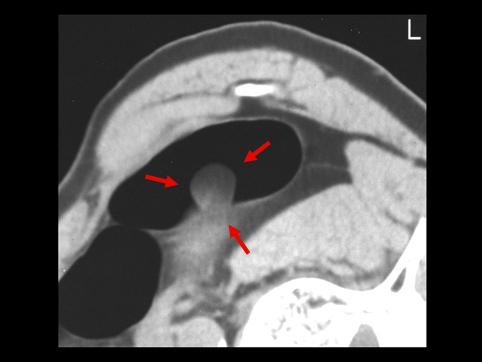

양성 비상피성종양 지방종 (대장)

A case of colonic lipoma which was diagnosed by multidisciplinary method.

양성 비상피성종양/지방종

대장/하행

20~24